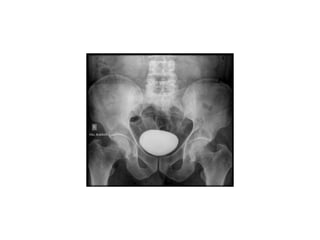

IVP